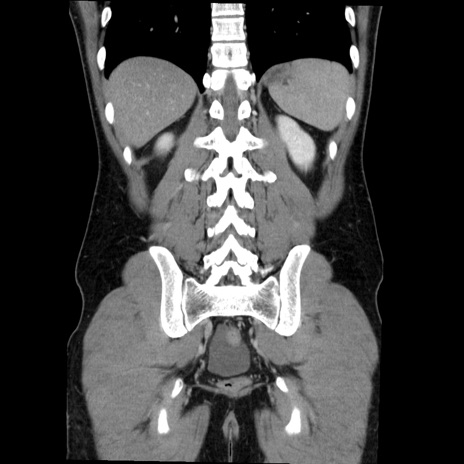

症例36(冠状断像)

【症例】20歳代 男性

【主訴】心窩部痛

【現病歴】今朝より上腹部痛あり。一旦軽快していたが再度出現したため救急要請。昨日夕に白身の魚を含む刺身を食べた。

【身体所見】BP 136/89mmHg、HR 74/min、BT 37.0℃、腹部:膨満、軟、心窩部に圧痛あり。反跳痛なし、筋性防御なし、腸雑音やや亢進あり。

【データ】WBC 17700、CRP 0.48